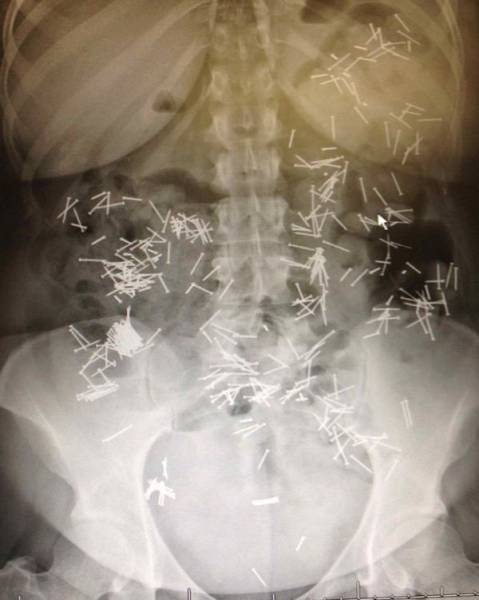

Nails. A lot of nails.